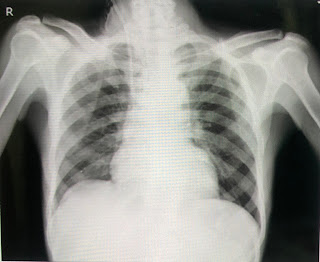

Clinical images:-